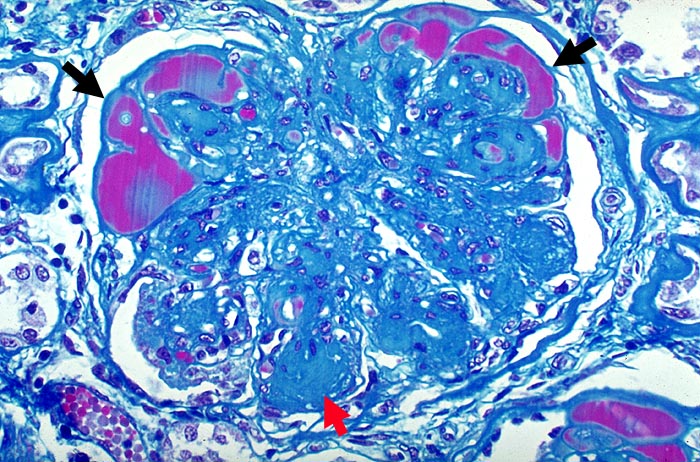

PathoPic – image database / PathoPic ID 1916 - Noduläre diabetische Glomerulosklerose Kimmelstiel-Wilson

Noduläre diabetische Glomerulosklerose Kimmelstiel-Wilson

Die Mesangiumarelae sind knotig verdickt. Die Knoten zeigen eine angedeutete Schichtung. Die peripheren Glomerulusschlinge sind hochgradig eingeengt. In Gefässpolnähe werden sie von Proteinthromben ausgefüllt (Exsudative Läsion).